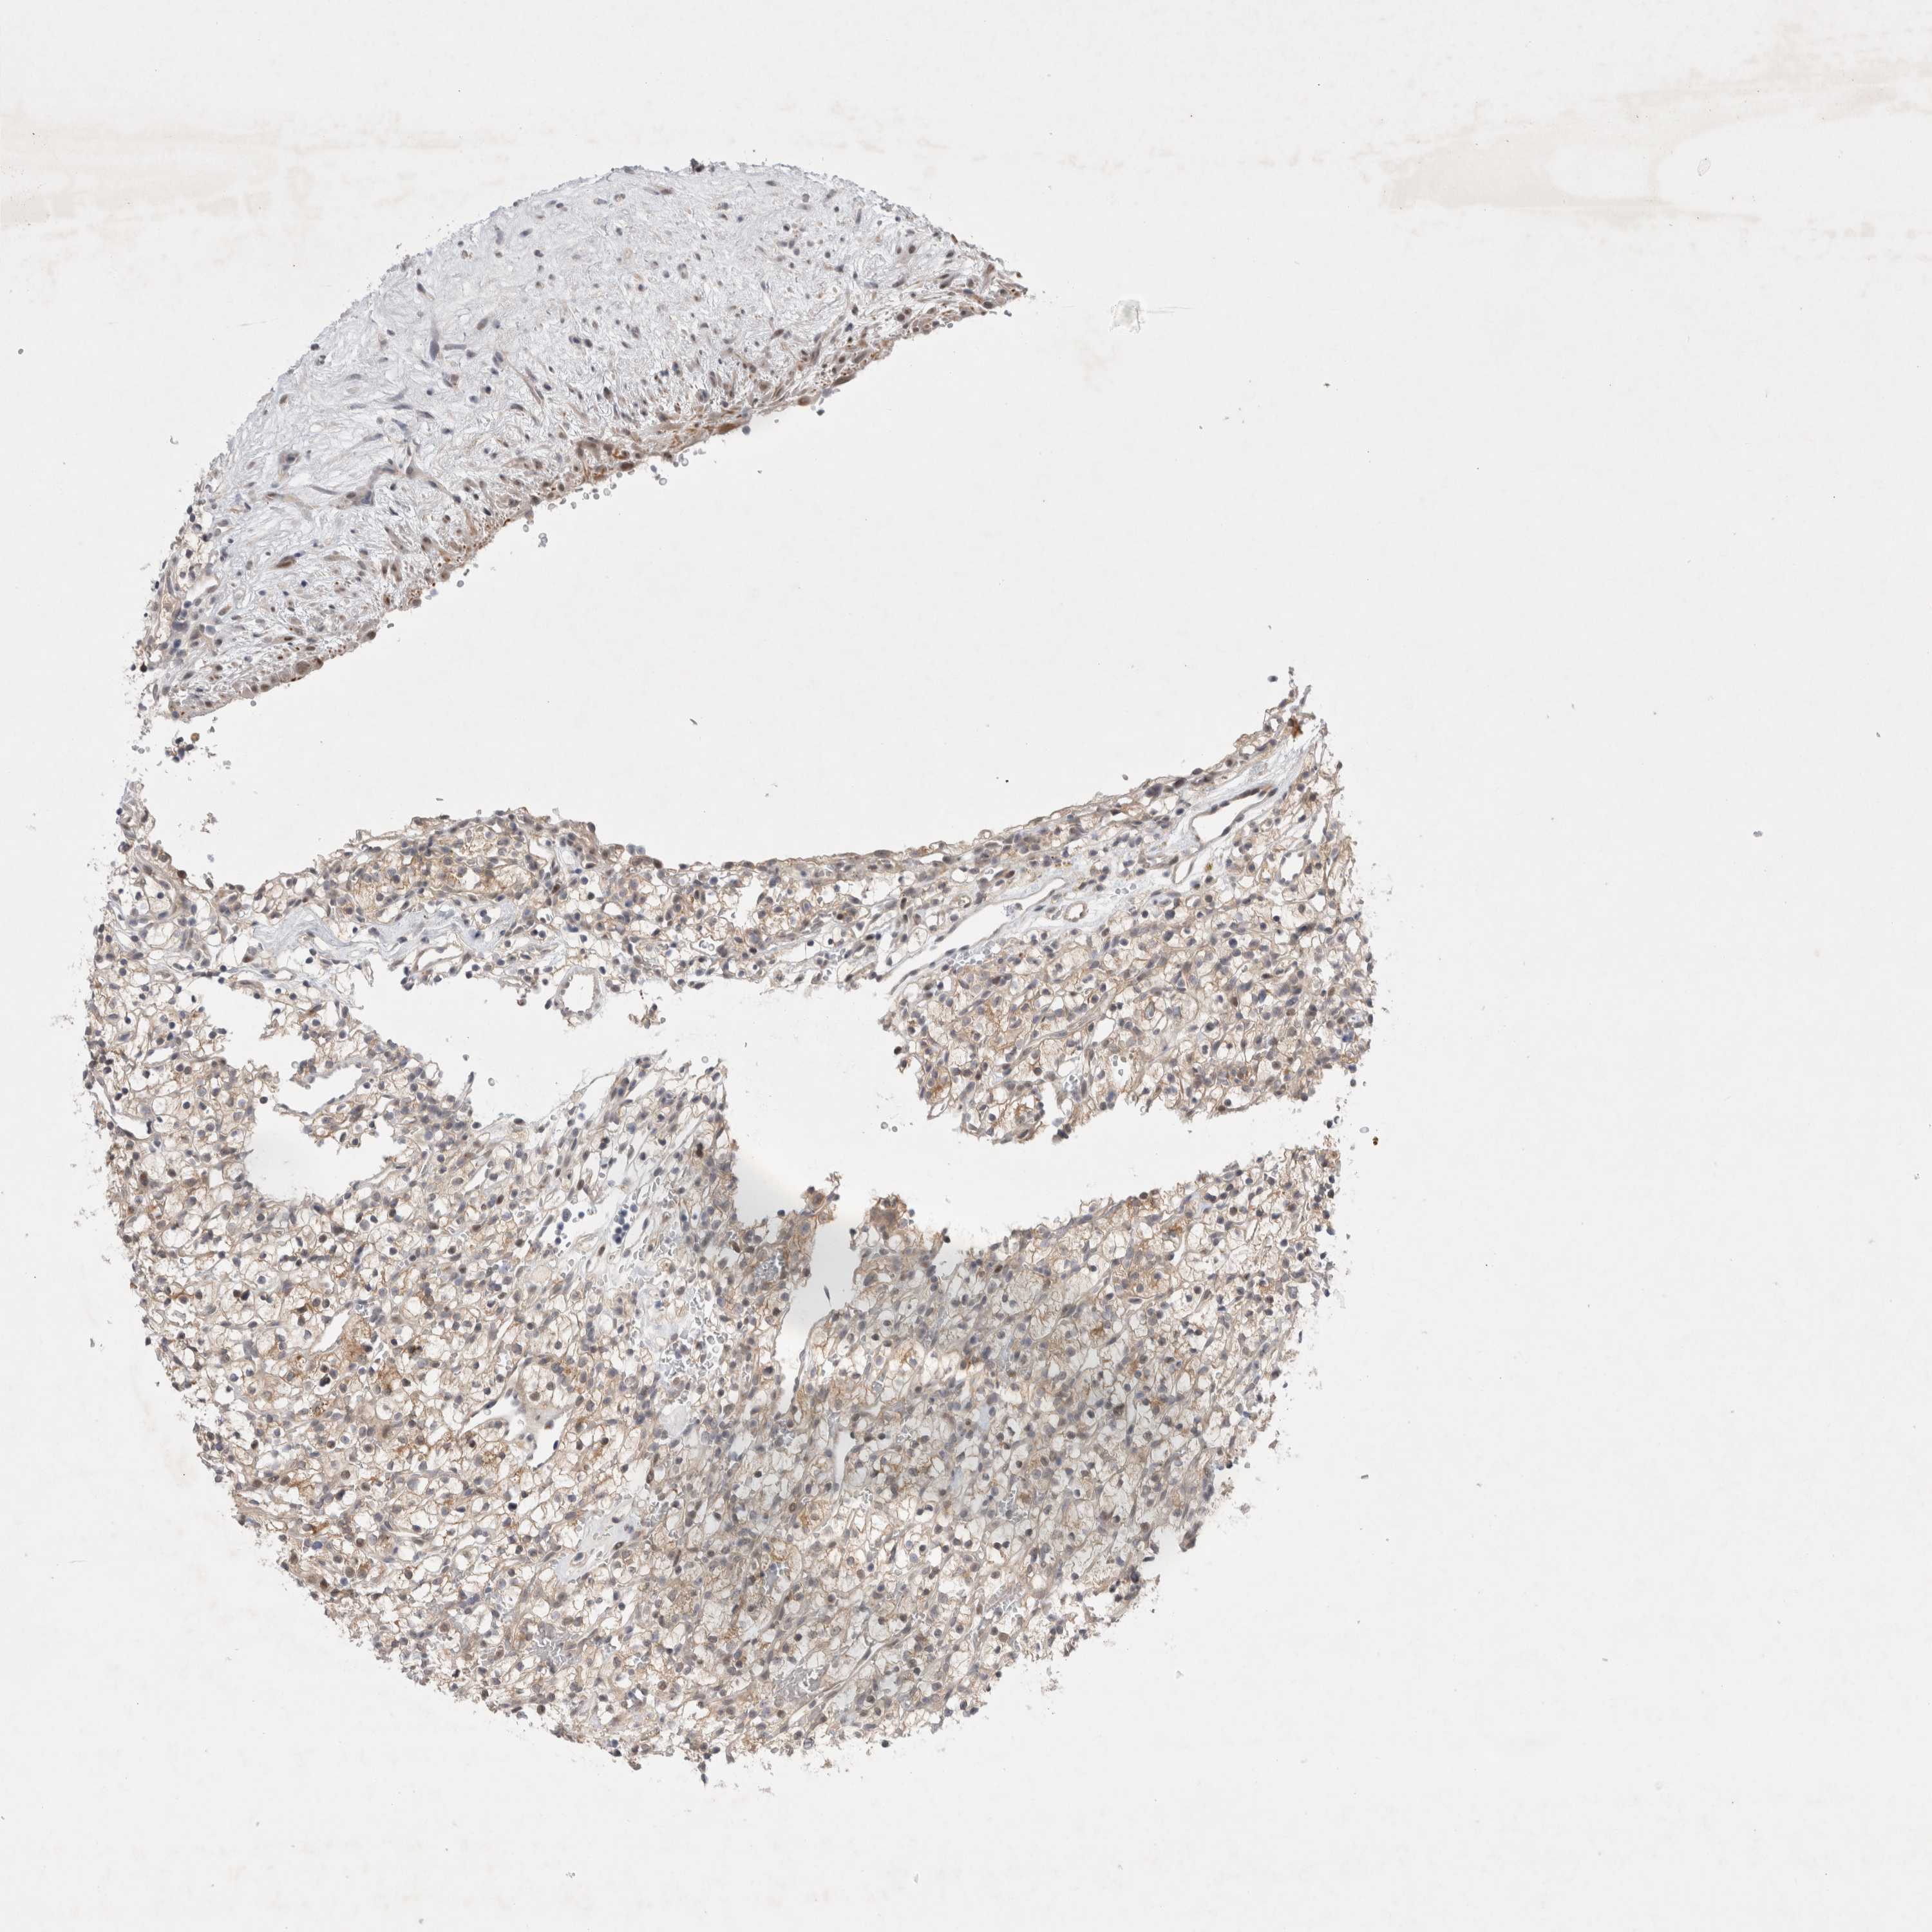

KIDNEY RENAL CLEAR CELL CARCINOMA (VALIDATION) - Interactive survival scatter ploti

The Survival Scatter plot shows the clinical status (i.e. dead or alive) for all individuals in the patient cohort, based on the same data that underlies the corresponding Kaplan-Meier plots. Patients that are alive at last time for follow-up are shown in blue and patients who have died during the study are shown in red.

The x-axis shows the expression levels (FPKM) of the investigated gene in the tumor tissue at the time of diagnosis. The y-axis shows the follow-up time after diagnosis (years). Both axes are complimented with kernel density curves demonstrating the data density over the axes. The top density plot shows the expression levels (FPKM) distribution among dead (red) and alive patients (blue). The right density plot shows the data density of the survived years of dead patients with high and low expression levels respectively, stratified using the cutoff indicated by the vertical dashed line through the Survival Scatter plot. This cutoff is automatically defined based on the FPKM cutoff that minimizes the p-score. The cutoff can be changed by dragging the vertical line or by entering a cutoff value in the square labeled "Current cut-off".

Under the Survival Scatter plot the p-score landscape (black curve; left axis) is shown together with dead median separation (red curve; right axis). Dead median separation is the difference in median mRNA expression between patients who have died with high and low expression, respectively. It is calculated as follows: median FPKM expression of dead patients with high expression - median FPKM expression of dead patients with low expression. This is intended to aid the user in visually exploring custom cutoffs and the associated p-scores and dead median separation.

Individual patient data is displayed and can be filtered by clicking on one or more of the category buttons on the top of the page. Categories describing expression level and patient information include: high, low, alive, dead, female, male and tumor stages. The scale of the x-axis can be toggled between linear and log-scale by clicking on the "x log" button. Mouse-over function shows TCGA ID, patient information and mRNA expression (FPKM) for each patient.

& Survival analysisi

Kaplan-Meier plots summarize results from analysis of correlation between mRNA expression level and patient survival. Patients were divided based on level of expression into one of the two groups "low" (under cut off) or "high" (over cut off). X-axis shows time for survival (years) and y-axis shows the probability of survival, where 1.0 corresponds to 100 percent.

WIPF2 is not prognostic in Kidney Renal Clear Cell Carcinoma (validation)

Best expression cut offi

Based on the FPKM value of each gene, patients were classified into two groups and association between prognosis (survival) and gene expression (FPKM) was examined. The best expression cut-off refers the FPKM value that yields maximal difference with regard to survival between the two groups at the lowest log-rank P-value. Best expression cut-off was selected based on survival analysis .

When clicking on this number, the vertical dashed line indicating cut-off, the interactive survival plot, and the Kaplan-Meier curve will be adjusted to show results based on the best expression cut-off.

: 18.82

TCGA RNA samplesi

RNA-seq data is reported as average FPKM (number Fragments Per Kilobase of exon per Million reads), generated by the The Cancer Genome Atlas (TCGA) .

Normal distribution across the dataset is visualized with box plots, shown as median and 25th and 75th percentiles. Points are displayed as outliers if they are above or below 1.5 times the interquartile range. FPKM values of the individual samples are presented next to the box plot.

Average pTPM 19.1

Number of samples 100